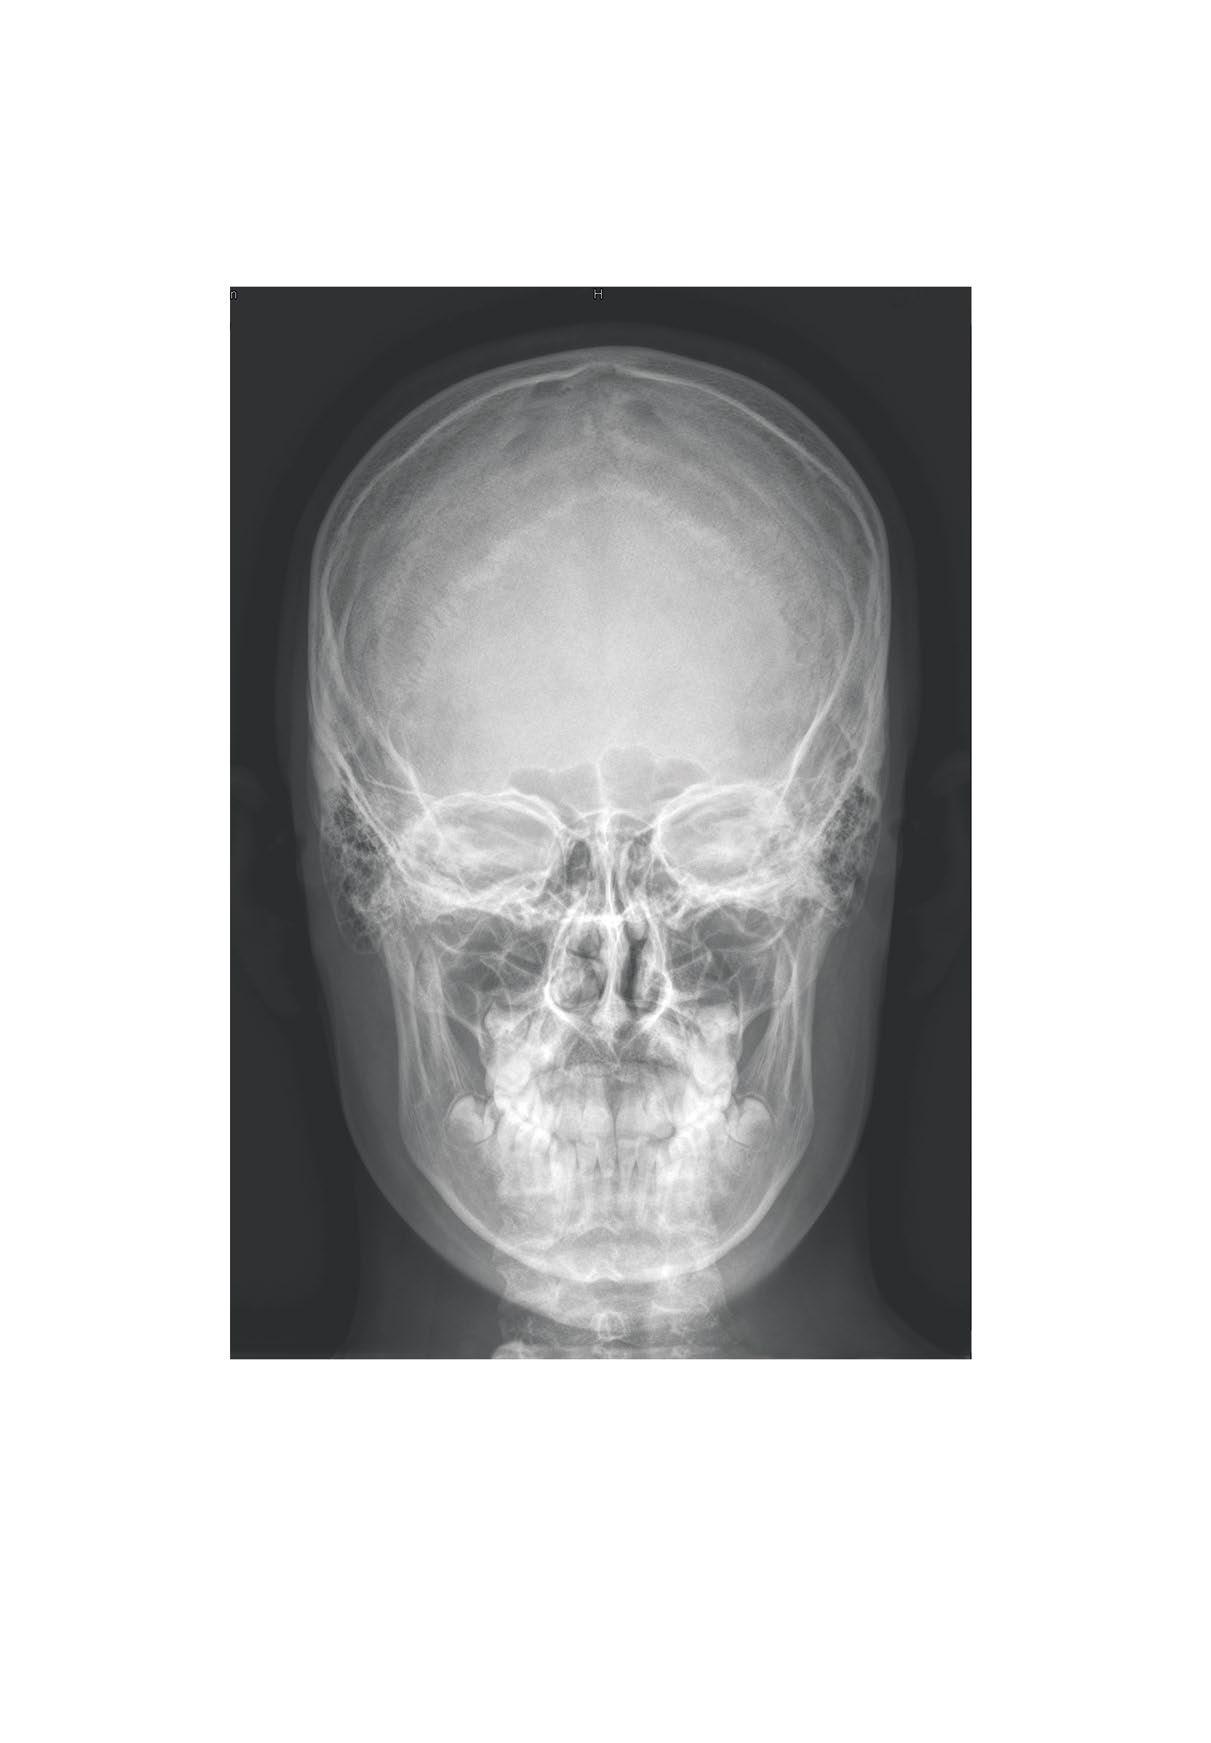

sutura sagittalis

concha nasalis media

concha nasalis inferior angulus mandibulae

Skull, X-ray, posterioanterior view, boy, 15 years Hlava

Cranium, RTG lebky, zadopřední projekce, chlapec, 15 let

sutura lambdoidea

sutura squamosa

linea temporalis superior os parietale

os occipitale

foramen mastoideum

squama ossis temporalis

meatus acusticus externus processus mastoideus processus styloideus

os zygomaticum

sutura coronalis

sutura sphenoparietalis

sutura sphenofrontalis

ala major ossis sphenoidalis

glabella os lacrimale os nasale sulcus nasolacrimalis

maxilla spina nasalis anterior

foramen mentale

sulcus arteriae meningeae mediae